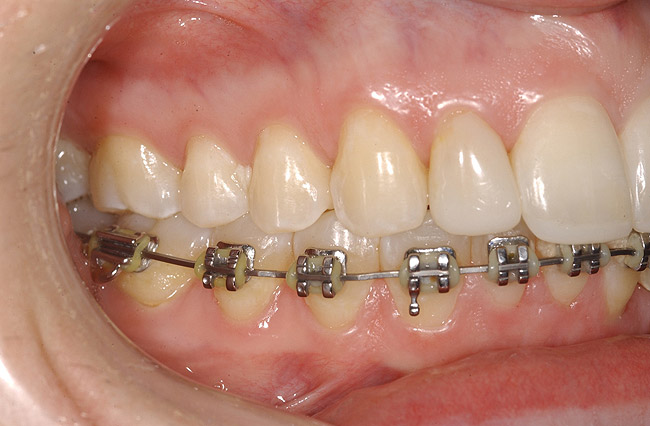

Figure 12  Right buccal view showing posterior occlusion established, canine guidance and proper space appropriation around peg lateral tooth No. 7, and intruded worn incisors.

Figure 12